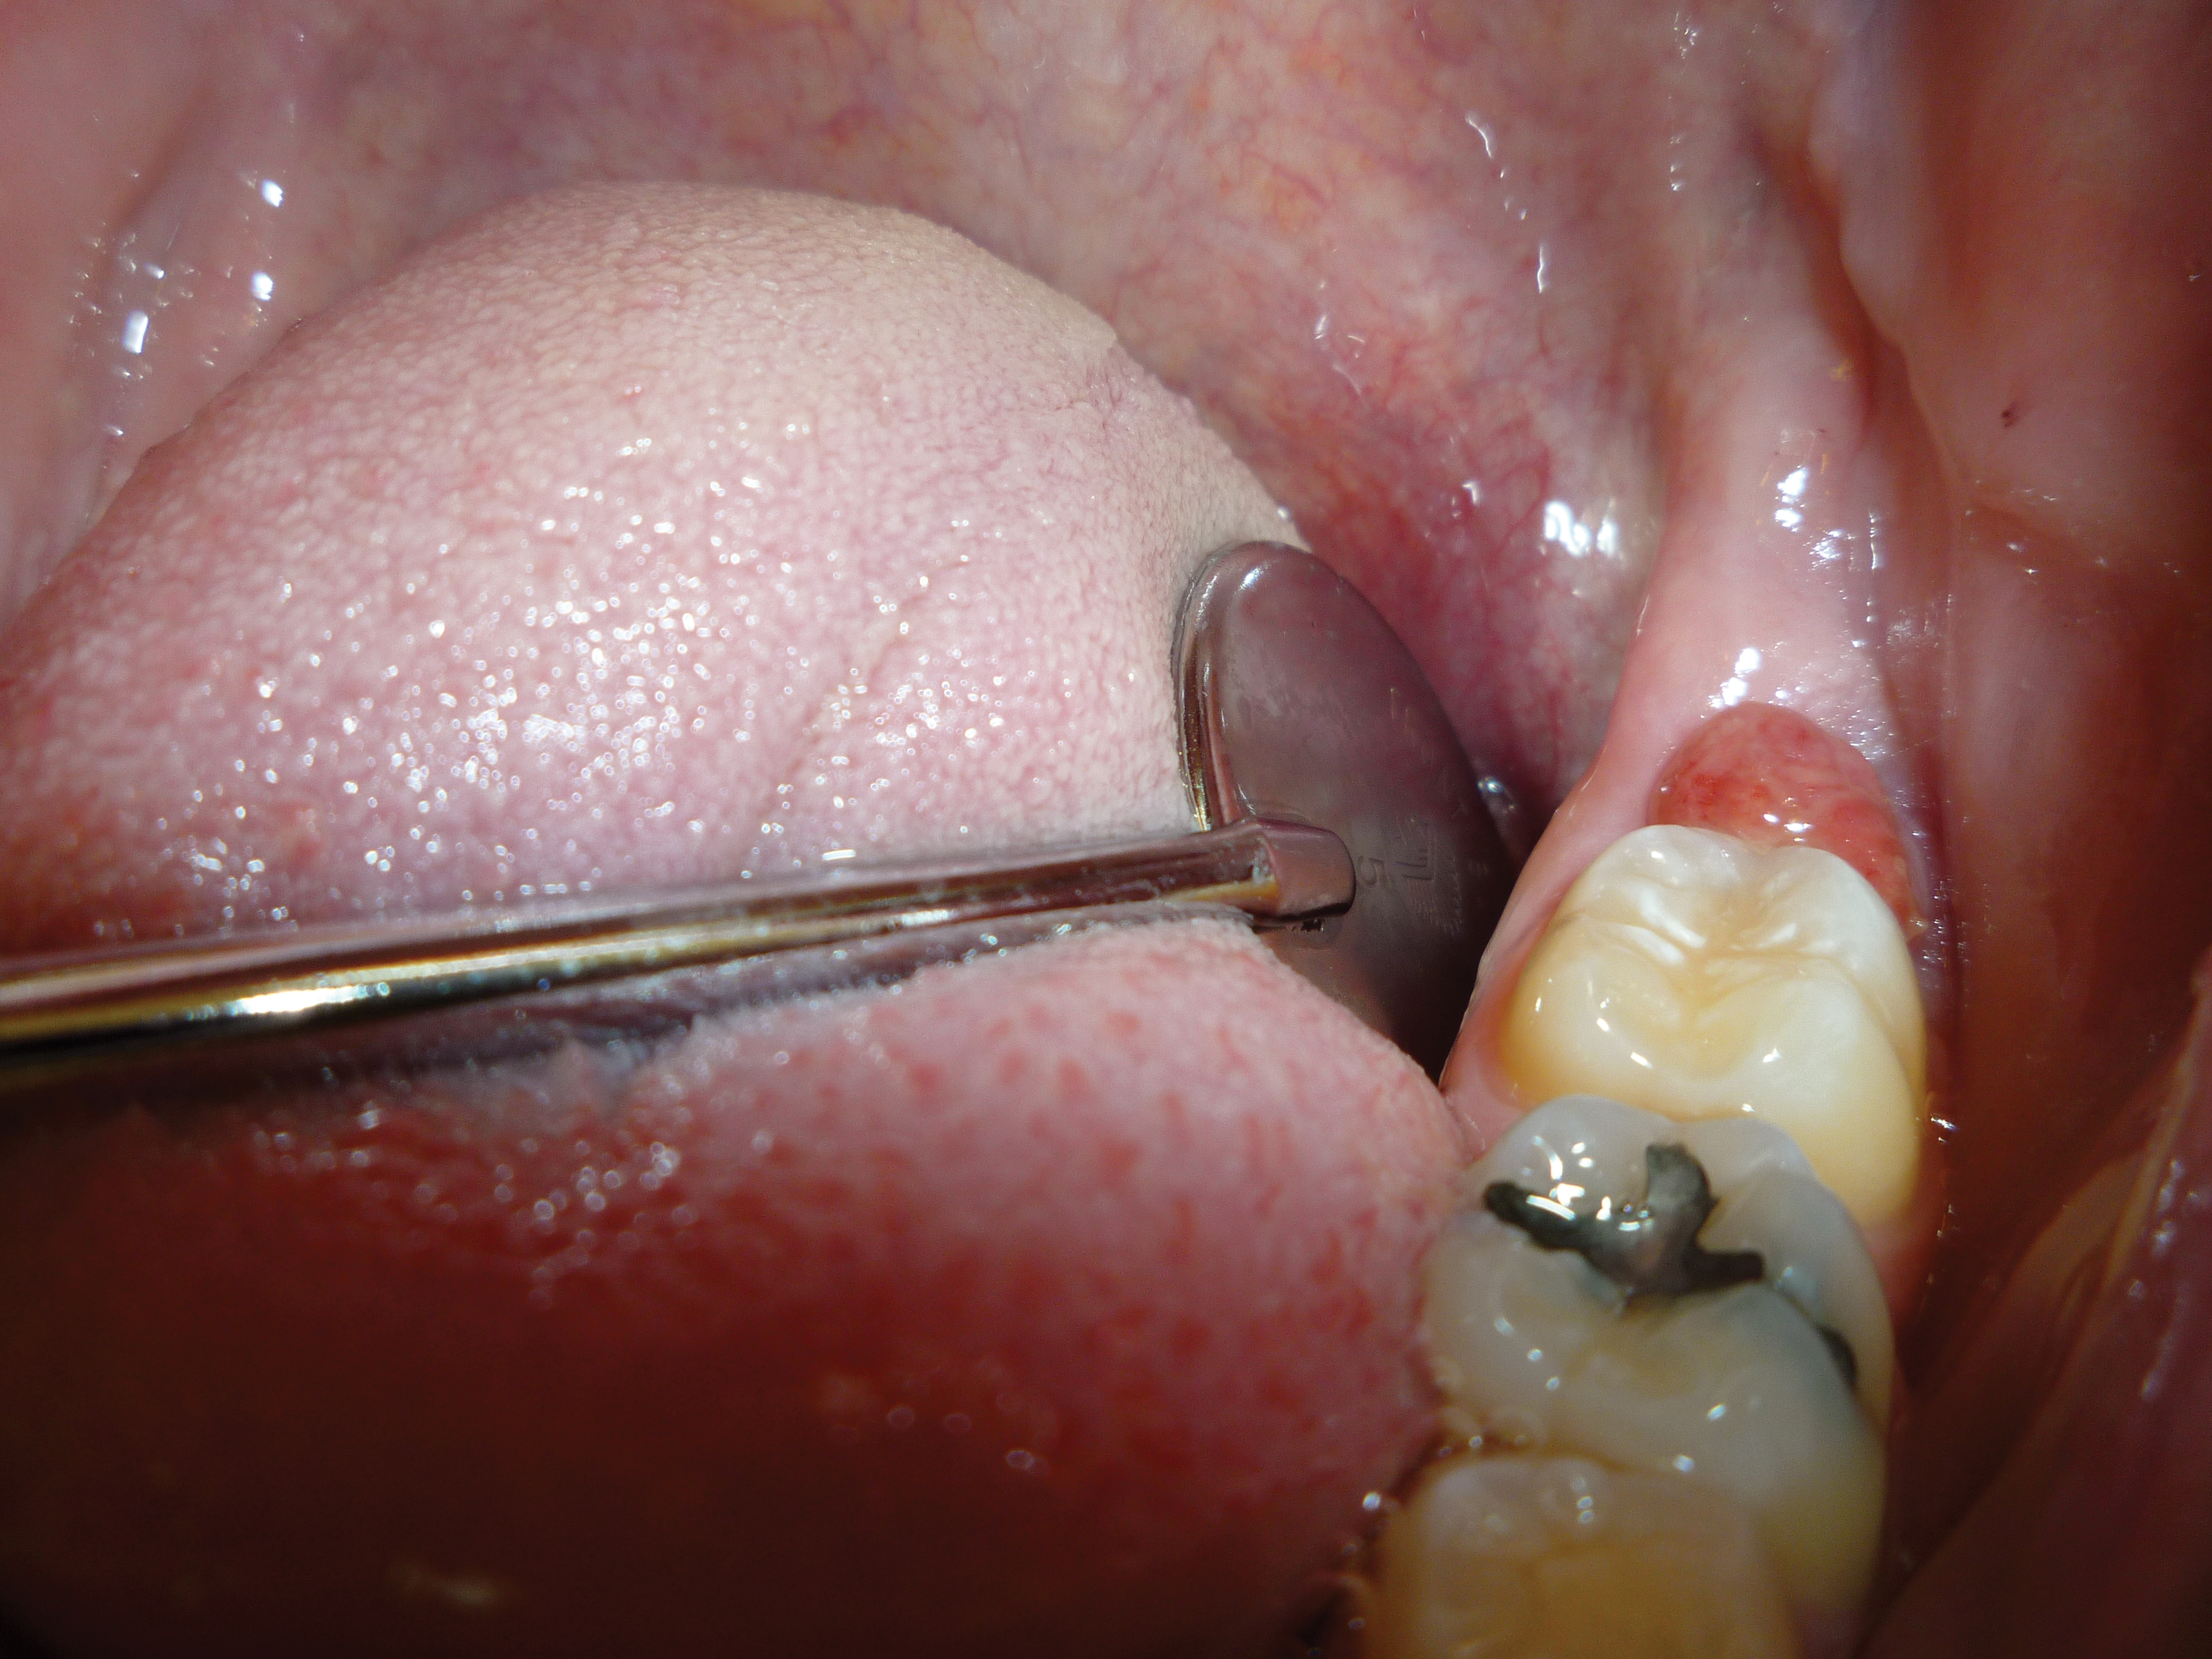

3. After the initial pass with the laser, the inflamed gingiva bled slightly and the surgeon defocused the beam by increasing the nozzle-to-tissue distance to quickly obtain hemostasis (Figure 6). Note the excellent visualization and the clear operatory field.

Fig 6. Excellent hemostasis after the completed ablation of the inflamed gingiva.

Figure 6